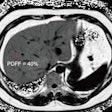

False-negative breast exams on the rise